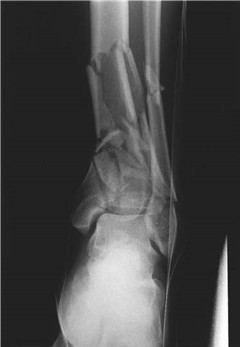

Describe what you see in this picture and explain your initial management.

This is an AP radiograph of the left ankle showing a multifragmentary pilon fracture.

I would perform an ATLS review and rule out concomitant injuries. I would then assess the neurovascular status of the aff ected limb and observe for signs of open injury or degloving. I would apply a temporary splint, provide analgesia, and obtain AP and lateral radiographs.